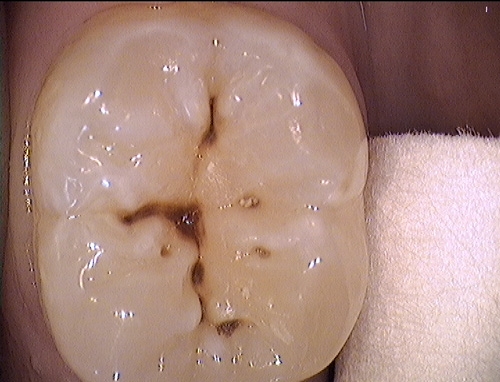

Trám răng-Hàn răng

Sâu răng là tổn thương tạm thời xuất hiện trên bề mặt của răng. Tổn thương này hình...

Trám phòng ngừa sâu răng

Đây là phương pháp dùng chất trám bít (nhựa composite hay glassionormer) hàn lên các hố rãnh trên...

Hàn răng- trám răng-các loại vật liệu hàn răng

Sâu răng là bệnh rất phổ biến, có thể gặp ở mọi lứa tuổi từ những trẻ răng...